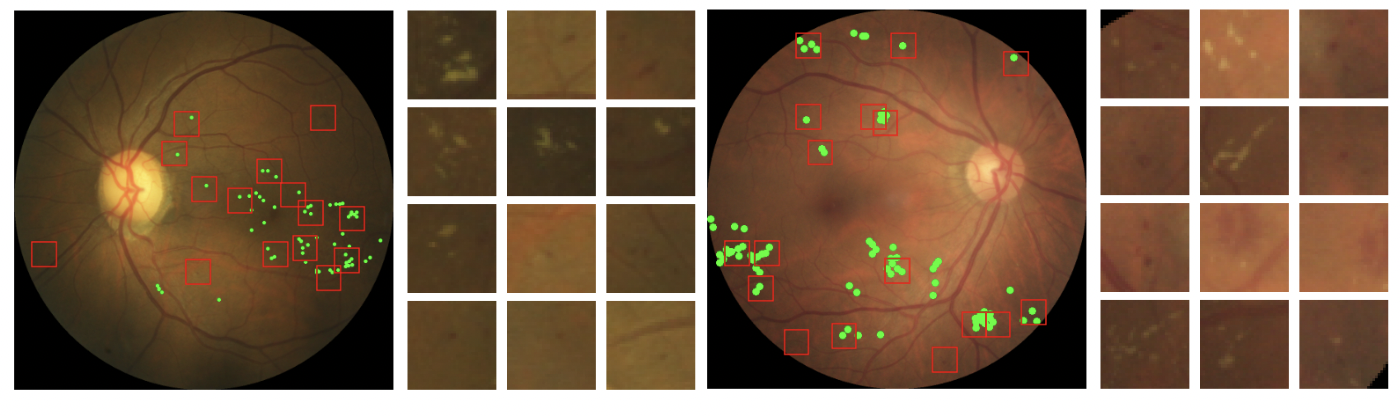

Sparse Activations for Interpretable Disease Grading

Kerol R. Donteu Djoumessi, Indu Ilanchezian, Laura Kühlewein, Hanna Faber, Christian F. Baumgartner, Bubacarr Bah, Philipp Berens, Lisa M. Koch

Proceedings of Machine Learning Research, 227, 1-17 (2023)

journal URL

preprint URL